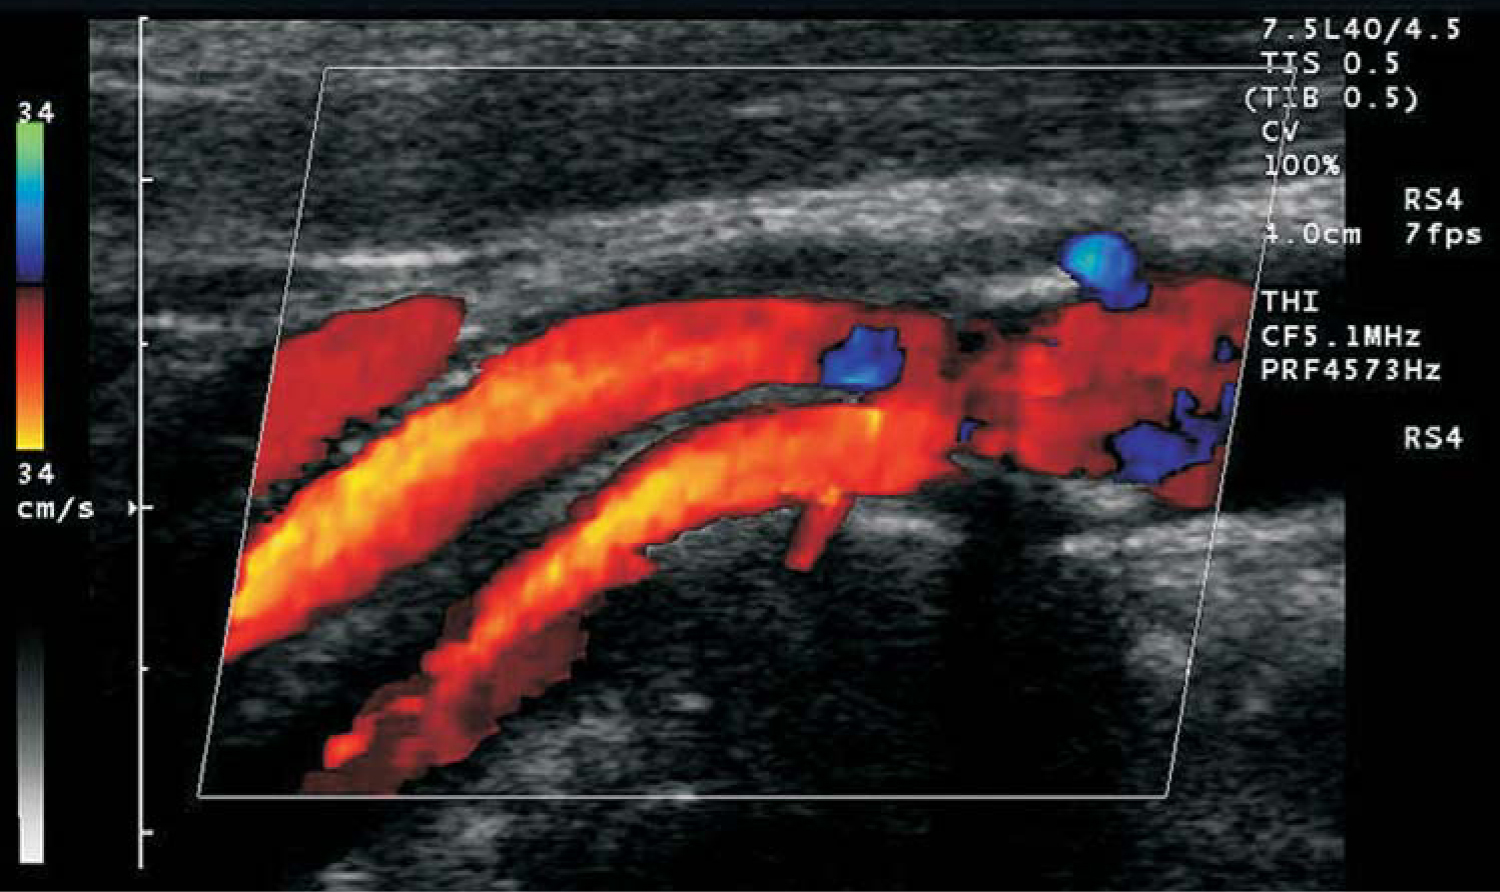

Admittedly, those phase shifts result from slightly different sets of blood cells being present in the interrogated volume from one pulse to the next and so are not, strictly speaking, Doppler shifts of individual scatterers. Nevertheless, as long as the change in scatterer distribution varies only slightly from pulse to pulse, CFI determines not only the average blood velocity but also a spectrum of velocities that can be color coded to represent forward and reverse blood flow. Such flow data are typically overlaid on the B-mode image in modern ultrasound scanners, as shown in figure 2.

PTO.v60.i3.44_1.f2.jpg

Figure 2. Color flow Doppler image showing blood flow in an artery. The blue regions show regurgitation—blood flow reversed from the principal flow indicated in orange.

(Image from Siemens/Acuson, 2003.)